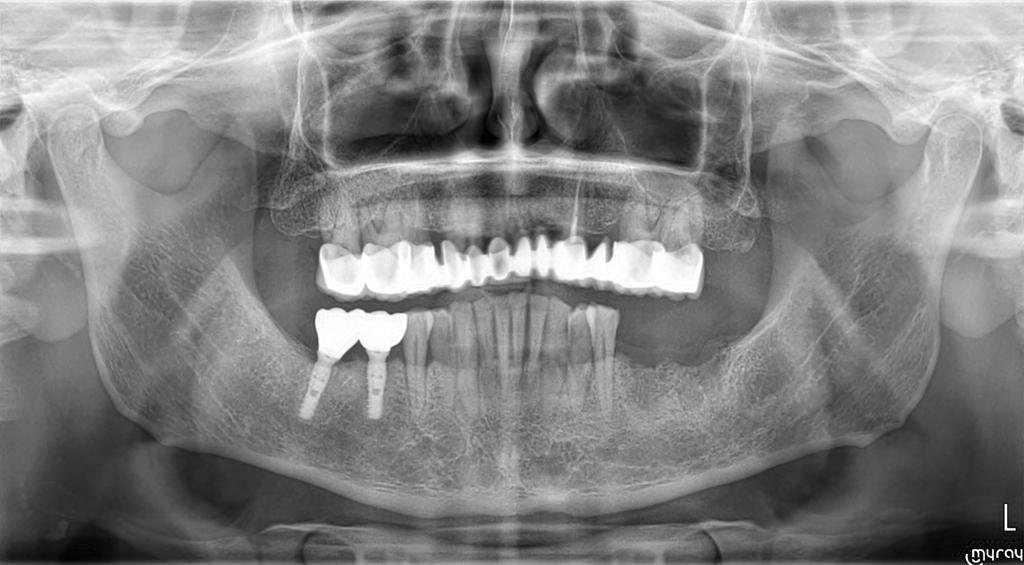

Case Presentation: A 42-year-old male patient with high diabetes and heavy smoking-alcohol use presented with multiple tooth loss. These systemic health factors posed potential risks for implant treatment. However, successful implant placement with Naxis implants was achieved in sites 46-47 to address the patient's dental needs. Approximately two years later, implants were also placed in sites 36-37 using Naxis implants.

Post-Treatment Evaluation: The patient continued smoking and alcohol consumption after implant surgery. However, evaluation of the long-term stability and success rates of the implants, based on X-ray images taken five years later, revealed that the Naxis implants were securely maintained. This demonstrates that successful implant treatment is possible despite the negative effects of systemic health factors, with regular follow-up and periodontal care.